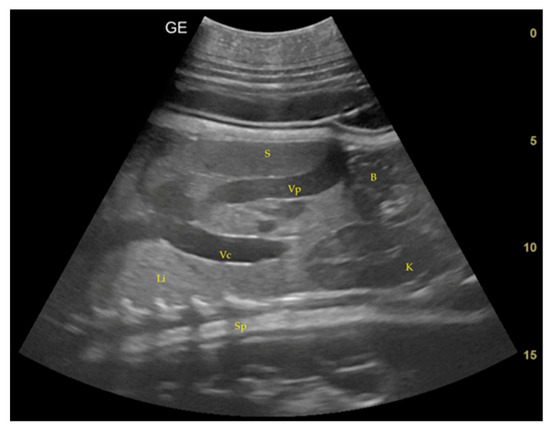

3.1. Changes in the Maternal Reproductive System

- Day 219 ± 3 days: It is also possible to recognize the eye as an anechoic cavitary structure (Figure 6). During the last month of pregnancy, it is possible to easily identify most of the abdominal organs such as the liver, spleen, intestine, and kidneys (Figure 7). In addition, the genitalia are visible and it could be possible to establish the sex of the fetus: in males, it is possible to identify the penis bone, which is obviously absent in females, but its visualization depends strongly on fetal position.